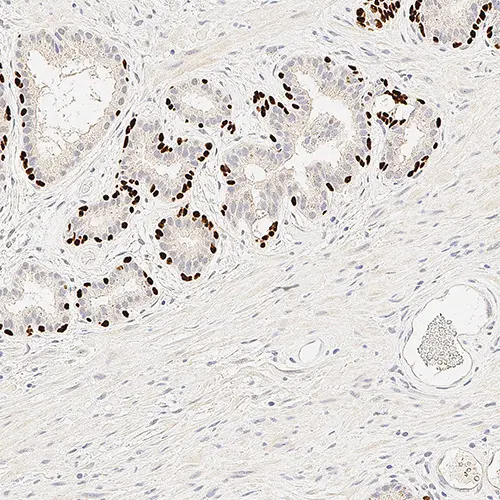

Human prostate: immunohistochemical staining for p63. p63: clone 7JUL

Das p63-Protein soll in einer Vielzahl gesunden Gewebes einschließlich proliferierender Zellen des Epithels, Gebärmutterhals, Urothel und Prostata exprimiert werden.

Berichten zufolge wird das p63-Protein bei Prostataadenokarzinomen nicht exprimiert. Seine veränderte Expression ist bei der Blasenkarzinogenese jedoch häufig zu finden.